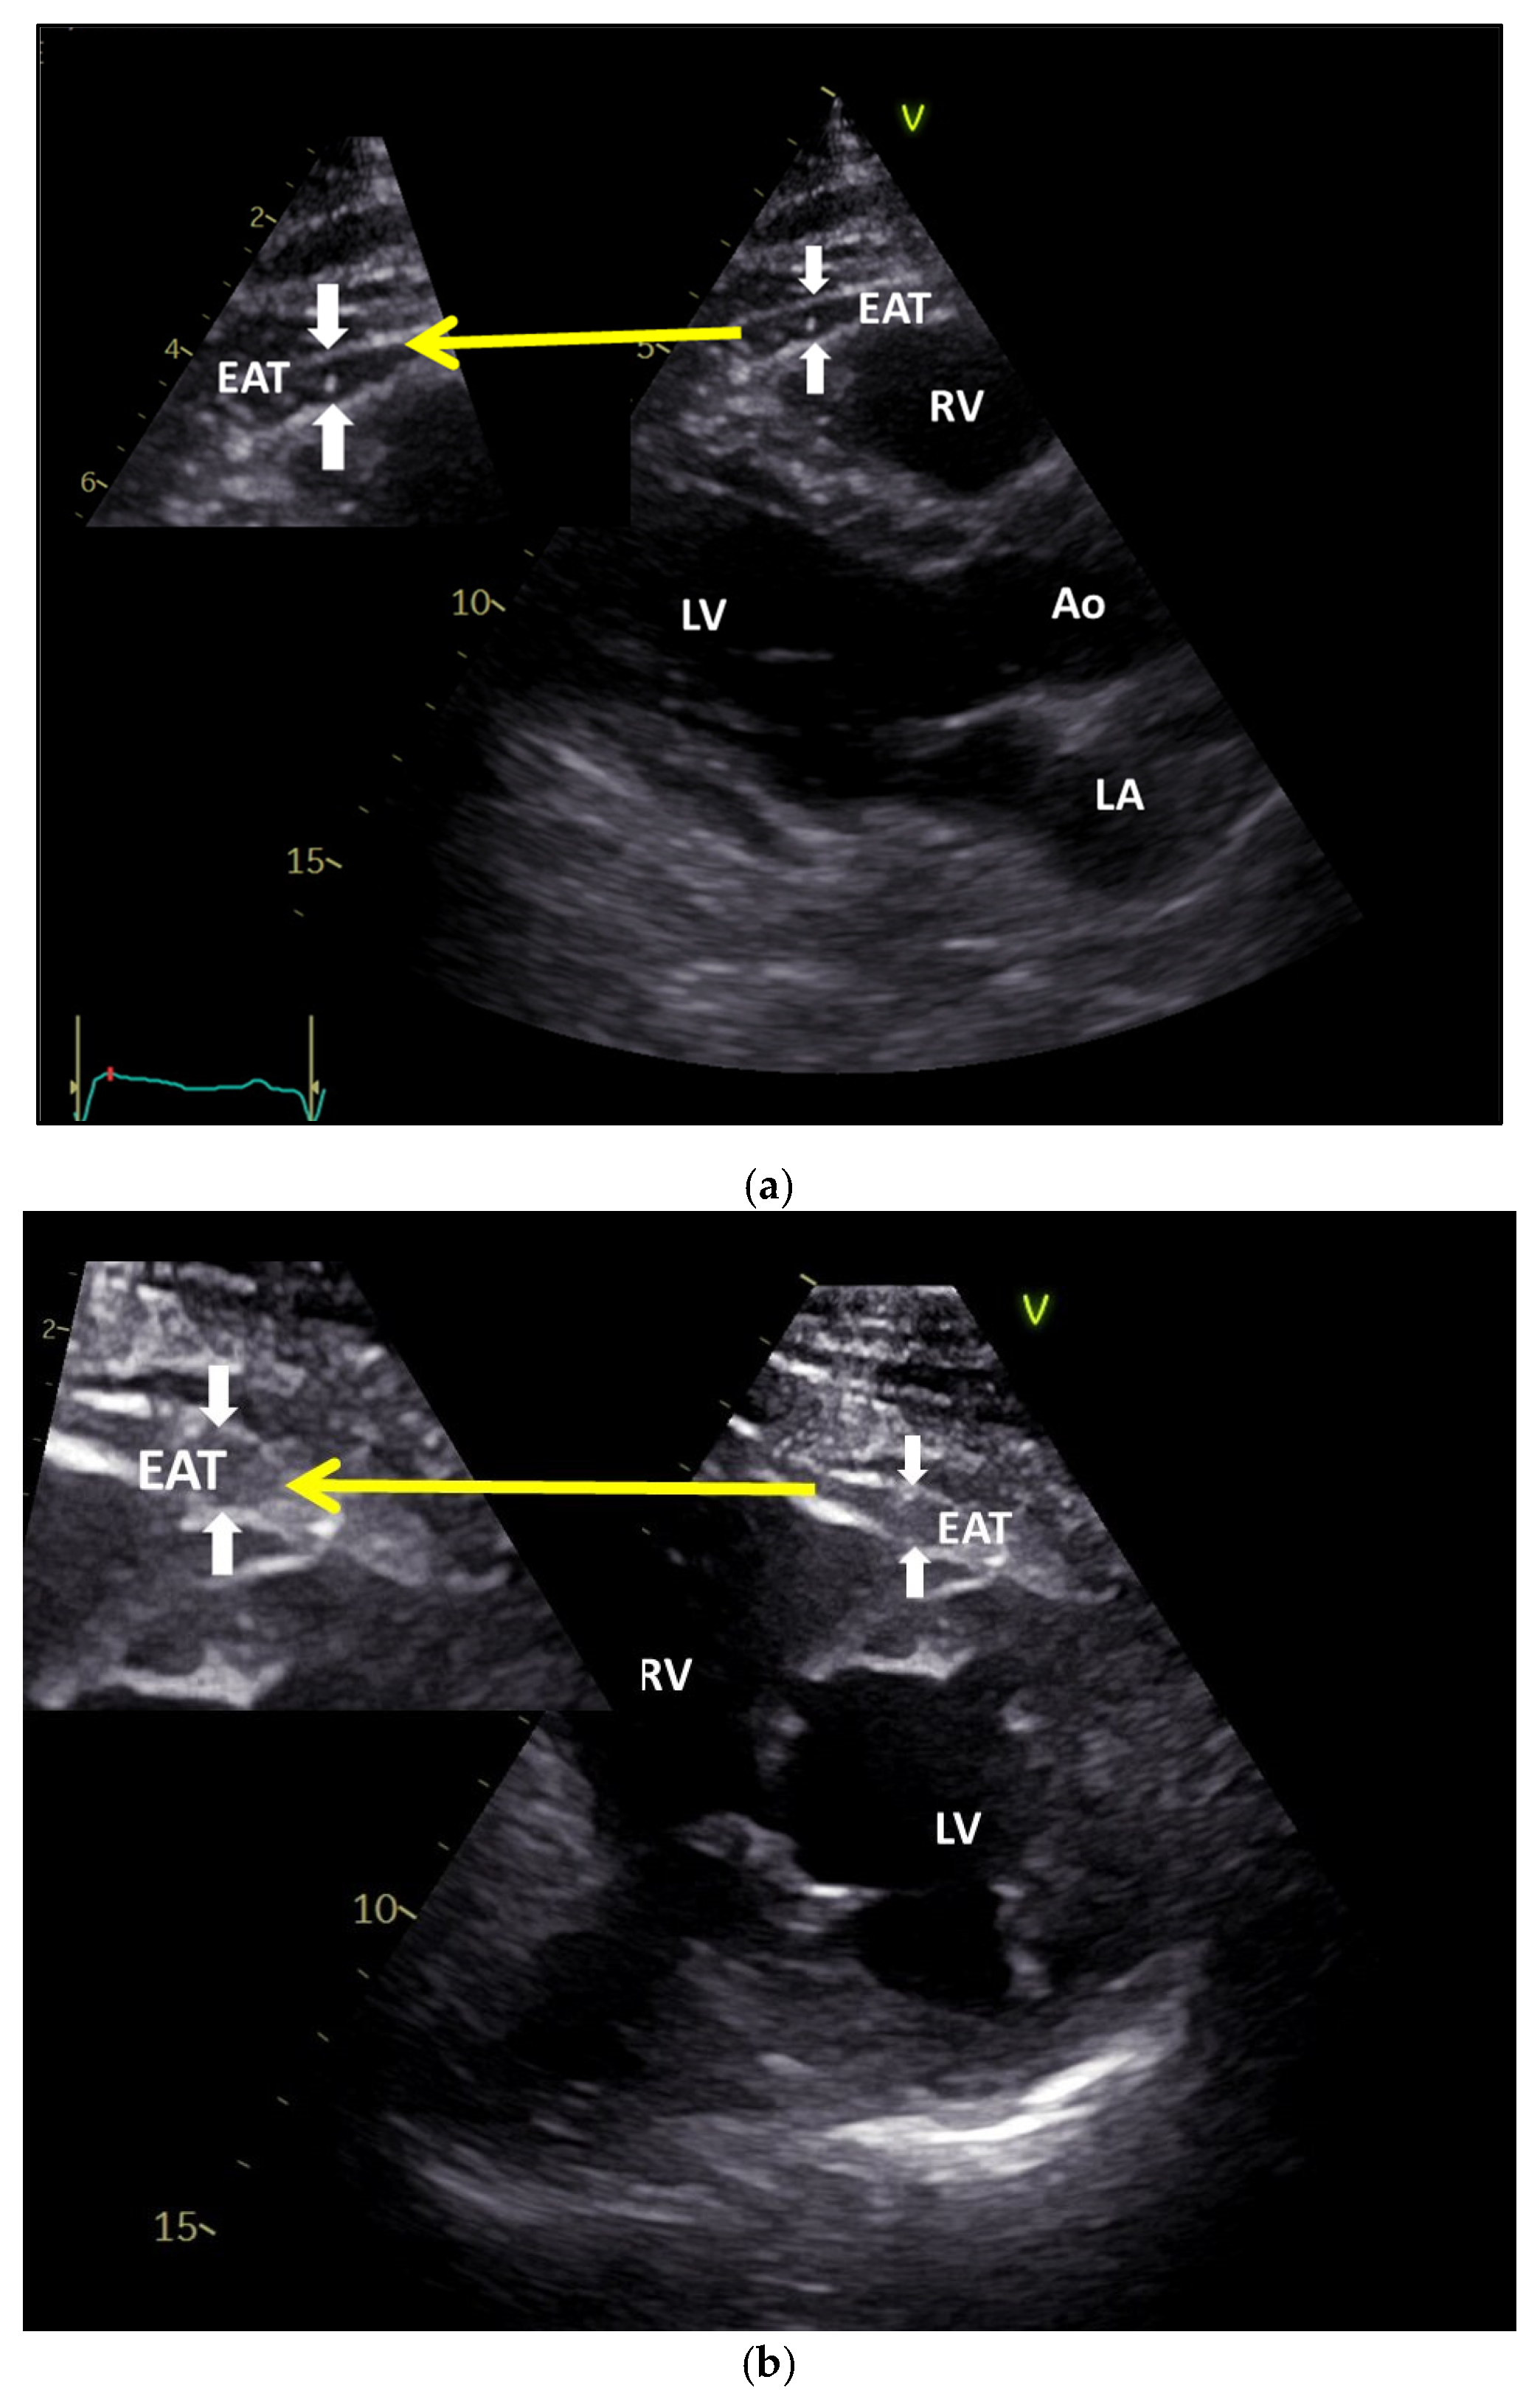

3.3. Non-Invasive Measurement of Epicardial Fat: Ultrasound, Computed Tomography (CT), and Magnetic Resonance Imaging (MRI)